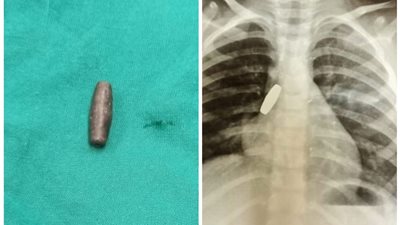

إنقاذ طفلة ابتلعت طلقة خرطوش في المنيا (صورة)

18/October/2021